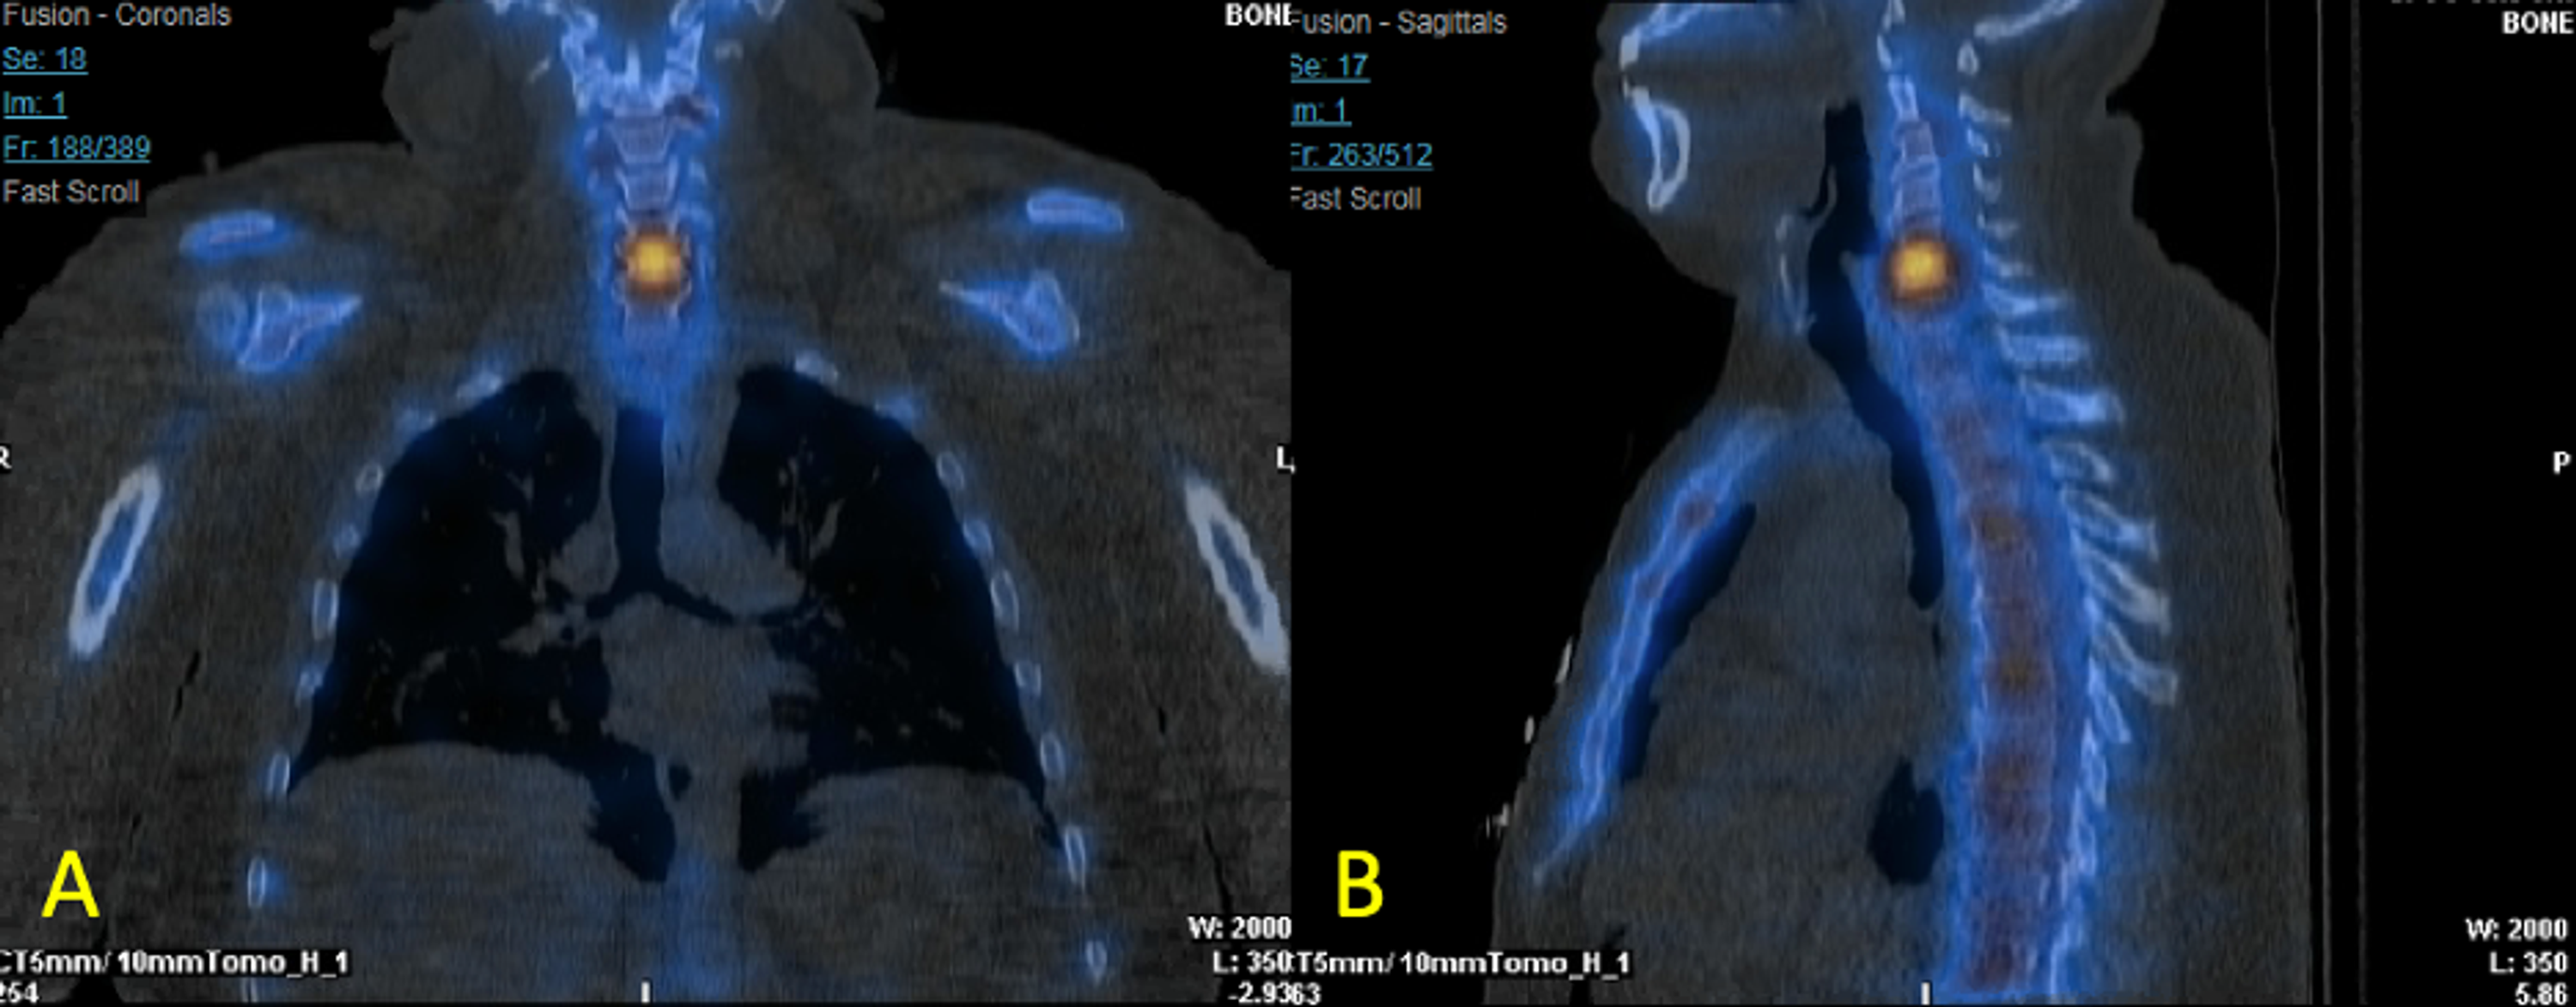

Increased Sacral Uptake on a Bone Scan with SPECT/CT in a Patient with What Spect Means It allows the clinician to assess the. What does the abbreviation spect stand for? Single photon emission computed tomography. Single photon emission computed tomography. This 3d scan allows doctors to assess the function of. Spect stands for single photon emission computerized tomography scan. See examples of spect used in a sentence. What Spect Means.

Nuclear Medicine Studies WholeBody Bone SPECTCT Scans For Cancer What Spect Means What does the abbreviation spect stand for? Single photon emission computed tomography. See examples of spect used in a sentence. It allows the clinician to assess the. Spect stands for single photon emission computerized tomography scan. This 3d scan allows doctors to assess the function of. Single photon emission computed tomography. What Spect Means.